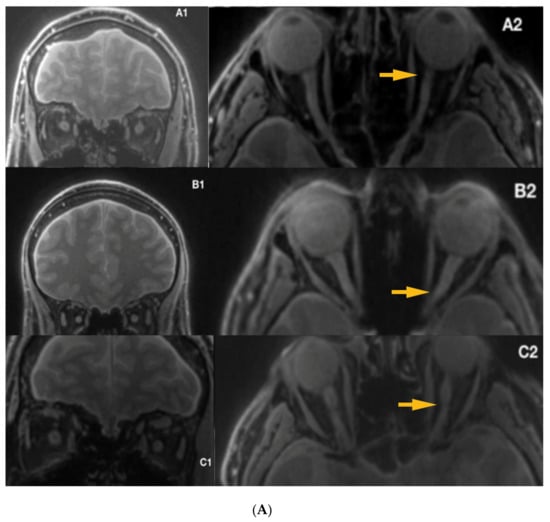

Silent-MT images obtained in a healthy control clearly distinguish the axonal part of the optic nerve and surrounding structures. The optic nerve is clearly visible as well as the surrounding CSF and the optic nerve sheath in the healthy individual. Silent-MT images showed good signal and strong contrast in the optic nerve, had excellent suppression of the fat surrounding the ONSC, and showed no motion artifact. In LHON patients hyperintense areas are visible along the whole optic nerve (Figure 2 and Figure 3). Moreover, the nerve itself looks thinner, with an irregular shape and structure. Abnormalities are mostly visible within the proximal and distal part of the optic nerve as well as within the optic disc area. Moreover, in this work we demonstrate that increasing the number of spokes per group to 192 increases the sequence time efficiency and reduces RF power deposition while maintaining significant MT contrast. There were no adverse events reported in any participant after the scanning.

Figure 2.

Hyper intensive area visible within the ONSC. ONSC, Optic Nerve Sheath Complex.